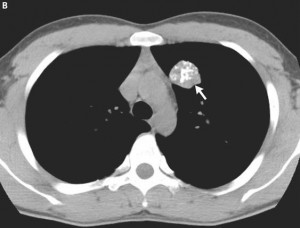

Una vez estudiados los hallazgos radiológicos que nos ofrece la radiografía simple, que en el caso que nos atañe se trata de un nódulo radiodenso en el lóbulo superior derecho, pasaríamos a realizar una prueba complementaria, que en este caso sería la TC simple. Hemos visto las ventajas que esta prueba complementaria tiene. Sin embargo, también se podrían realizar otras pruebas de imagen, como la TC con contraste, la resonancia magnética o el PET-TAC. Para el diagnóstico de un tumor carcinoide estaría indicado realizar un TC con contraste, ya que son tumores normalmente hipervasculares, por lo que con el contraste realzan muy bien. Ante la sospecha de un tumor carcinoide (tumor neuroendocrino) otra prueba diagnóstica que se podría realizar sería un octreoscan. Este estudio radiológico se trata de una gammagrafía de receptores de somatostatina. Se trata de inyectar en el paciente un análogo de la somatostatina, y observar si el nódulo realza, ya que los tumores neuroendocrinos tienen alta densidad de receptores para somatostatina. Además, este tipo de estudios no sólo nos localiza el tumor, sino que también nos pueden informar sobre posibles metástasis que existan.

El patrón radiológico observado nos lleva a pensar en un tumor carcinoide, un tumor neuroendocrino que se origina de células endocrinas de los bronquios principales y de los conductos de las glándulas mucosas. Es un tumor central, de los bronquios principales, que crece como una masa que ocluye parcialmente el bronquio. Al menos ¾ del tumor es intramucoso (típico crecimiento en iceberg o reloj de arena). Representan el 1-2% de las neoplasias traqueobronquiales. La imagen radiológica es una lesión bien definida, redondeada u ovalada de 2-5 cm. Pueden calcificar. Suelen ser hipervasculares y realzar en la TC con contraste. Raramente tienen un patrón invasivo o son multifocales. Hay tumores carcinoides atípicos, que son de mayor tamaño, presentan necrosis, suelen localizarse en la periferia del árbol bronquial y pueden ser localmente invasivos. Los tumores carcinoides tienen varias formas de presentación:

1. Masa hiliar o perihiliar: estrechan, deforman o comprimen la vía aérea adyacente. Raramente tienen un patrón invasivo o son multifocales. Pueden presentar calcificaciones de forma difusa. Suelen ser hipervasculares con realce en la TC con contraste. Ambos puedes relacionarse con adenopatías mediastínicas.